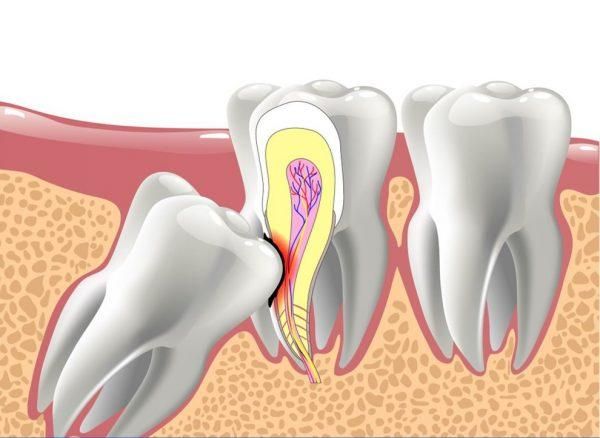

Wisdom teeth, also known as third molars, are complex due to their deep roots and multiple ligaments. If your wisdom tooth is impacted, you need to visit a dentist for prompt treatment. At Linh Xuân Dental, patients receive thorough exams and X-rays. If the tooth is abnormal, extraction will be recommended. If the tooth is newly erupted and not affecting health, you'll receive guidance on managing pain during the eruption.